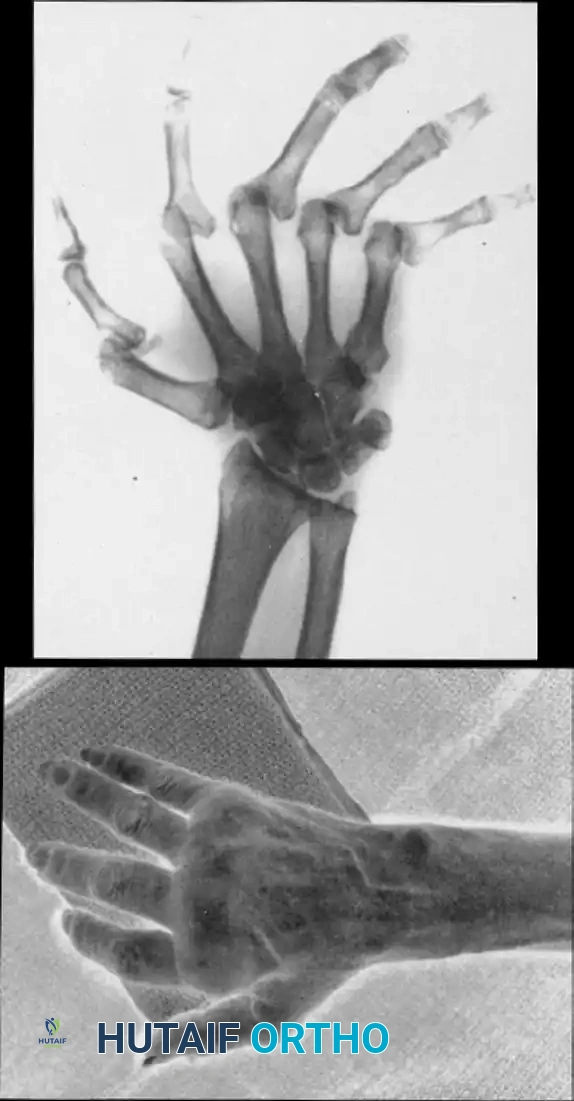

FIGURE 73-34 A and B: Preoperative clinical and radiographic presentation of a Type I thumb deformity, demonstrating fixed finger metacarpophalangeal joint subluxations with severe degenerative changes and ulnar translocation of the wrist, alongside a relatively preserved midcarpal joint.

Radiographic Templating

Standard posteroanterior (PA), lateral, and oblique radiographs of the hand and wrist are mandatory. Templating is utilized to estimate the size of the medullary canals of the metacarpal and proximal phalanx. The surgeon must assess the degree of bone loss, the presence of cystic changes, and the overall alignment of the carpus, as proximal instability (e.g., ulnar translocation of the carpus) can compromise distal surgical outcomes.

FIGURE 73-34 C and D: Postoperative radiographic appearance demonstrating successful radioscapholunate fusion, metacarpophalangeal implant arthroplasty with excellent implant seating, and concurrent thumb interphalangeal joint fusion to correct complex rheumatoid deformities.